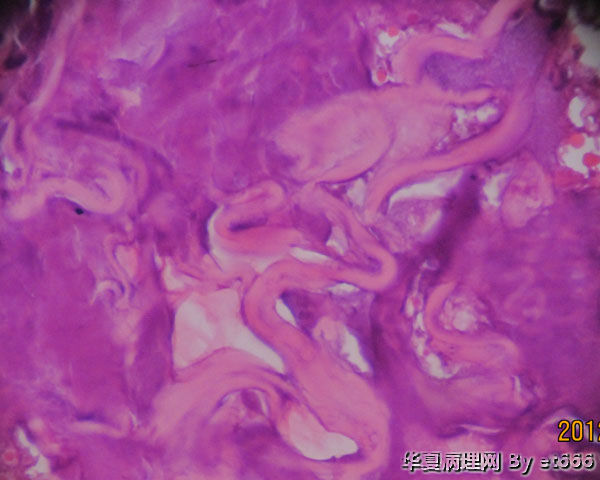

患者 75 腹股沟淋巴结活检 )送检软组织内可见片状干酪样坏死物,边缘有炎性肉芽组织,形态符合结核性病变。抗酸杆菌染色(-), 结核杆菌DNA检测(+)。在另一部位可见如图物质 不知是 .......请老师专家们赐教。

真菌菌丝?异物?其他?

有可能是隐球菌

会不会是寄生虫啊。照几张病变周边的反应性区域看看。

再传几张 。 其实我发报告的时候没有看见这些东西。后来有其他原因再看时发现这些物质的,可能这些物质颜色淡不显眼吧.

像是真菌

是的,而且是中空的。

考虑是寄生虫